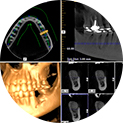

Компьютерная томография – используется в имплантологии и ортодонтии, где врачу требуется подробный снимок, отражающий состояние не только зубов, но и костной ткани, а также окружающих мягких тканей, может проводиться как для обеих челюстей, так и непосредственно для конкретного участка. |